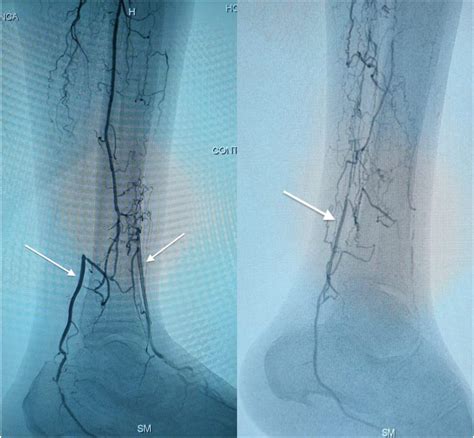

• Angiography: This invasive procedure involves injecting a contrast dye into the arteries and using X-rays to visualize the blood flow. It provides detailed images of the arteries and can help identify the location and extent of blockages.